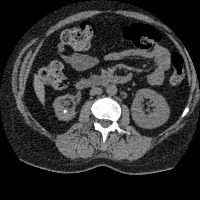

Regiao Renal

RegiaoRenal

regiao_renal